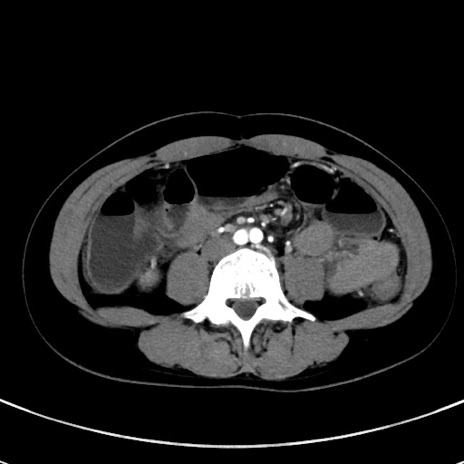

症例17(横断像)

【症例】20歳代女性

【主訴】嘔吐、下腹部痛

【現病歴】昨日夕食後に嘔吐し下腹部痛が出現。本日になっても嘔吐持続し改善しないため来院。

【身体所見】意識清明、BT 37.2℃、BP 108/67mmHg、腹部:平坦、やや硬、下腹部正中から右にかけて圧痛あり、反跳痛軽度あり、tapping pain(+)。

【データ】WBC 13600、CRP 14.94